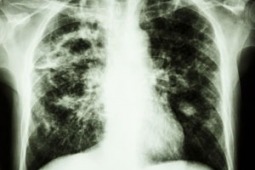

Samoistne włóknienie płuc jest przewlekłym, postępującym procesem zapalnym o nieznanej przyczynie, powodującym włóknienie tkanki płuc, a w efekcie spadek ich pojemności i trudności w wykonywaniu prostych codziennych czynności, takich jak chociażby chodzenie czy toaleta. Rokowanie w tej chorobie jest zawsze niepomyślne, a średni okres przeżycia krótszy niż w przypadku wielu nowotworów złośliwych, takich jak np. rak piersi, prostaty czy jelita. Zaledwie 25 proc. chorych przeżywa 5 lat od momenty rozpoznania. Na podstawie danych zebranych w państwach europejskich oraz Stanach Zjednoczonych szacuje się, że na samoistne włóknienie płuc zachorowuje rocznie ok. 5 osób na każde 100 tysięcy. W Polsce liczba ta szacowana jest na około 1 800 osób rocznie. Rzadkie występowanie choroby powoduje, że większość lekarzy nie rozpoznaje jej, co jest przyczyną błędów i opóźnień w diagnozie, stosowania nieprawidłowego leczenia i narażania chorego na działania niepożądane, a systemu ubezpieczeń na dodatkowe koszty.